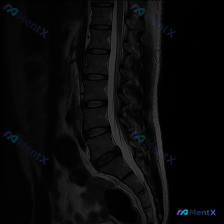

整理到一份腰椎MRI的影像分析资料,最初的问题很直接:「这张图里能观察到脊柱侧弯吗?」 先看已有的影像信息: - 序列:腰椎MRI T2矢状位 - 明确发现:L1/2到L5/S1椎间盘弥漫性脱水低信号,L4/L5、L5/S1向后膨出压迫硬膜囊前缘,部分椎体终板有许莫氏结节,生理前凸存在,序列尚可,无...

整理到一份腰椎影像资料,有点意思,拿出来和大家讨论。 资料是腰椎矢状位T2加权像,先说说能看到的表现: 1. 多节段椎间盘信号明显减低(黑盘征),L3/4、L4/5、L5/S1椎间隙还有不同程度塌陷; 2. L3/4、L4/5、L5/S1都有椎间盘突出,硬膜囊受压,L4/5、L5/S1看起来受压更明...